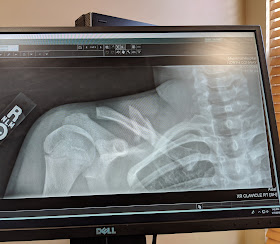

So, John's follow-up appointment for his shoulder surgery went well, and I finally got pics of the x-rays. The first one, you can see the "dagger" bone that was about to break through the skin. Ouch! The second is obviously the repair. John thought it looked like a bug in his shoulder. Haha.